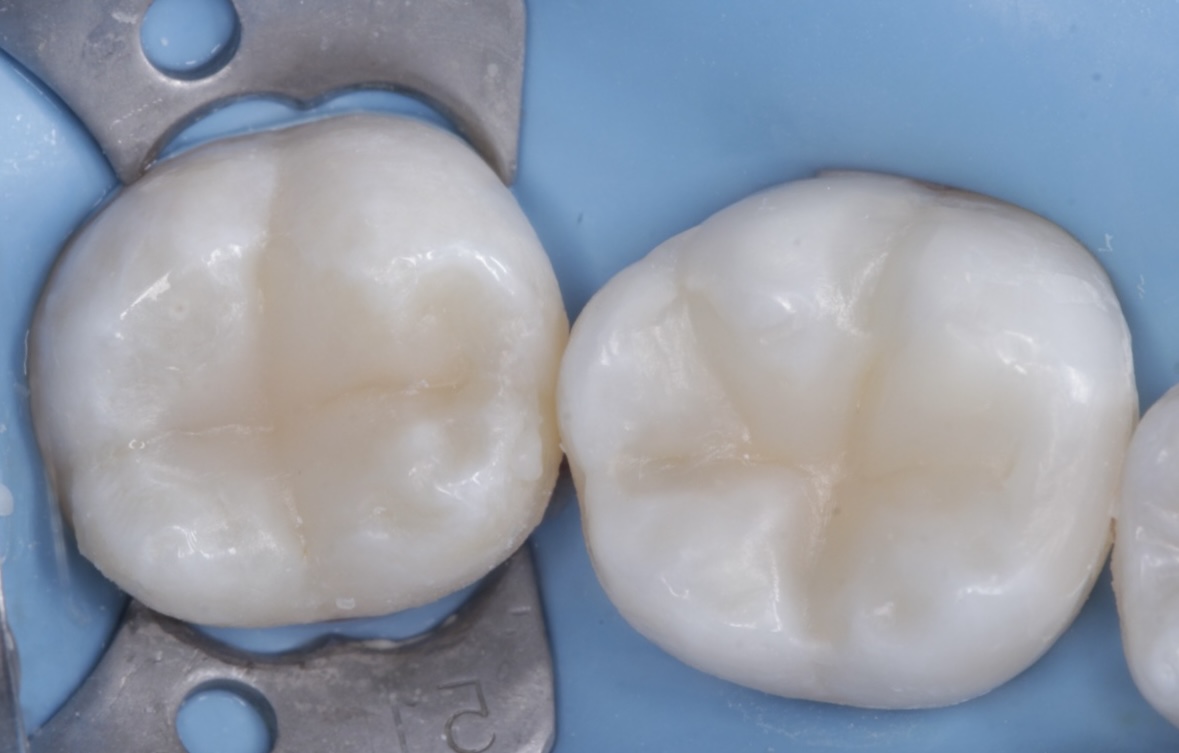

Детский и подростковый врач-стоматолог, терапевт